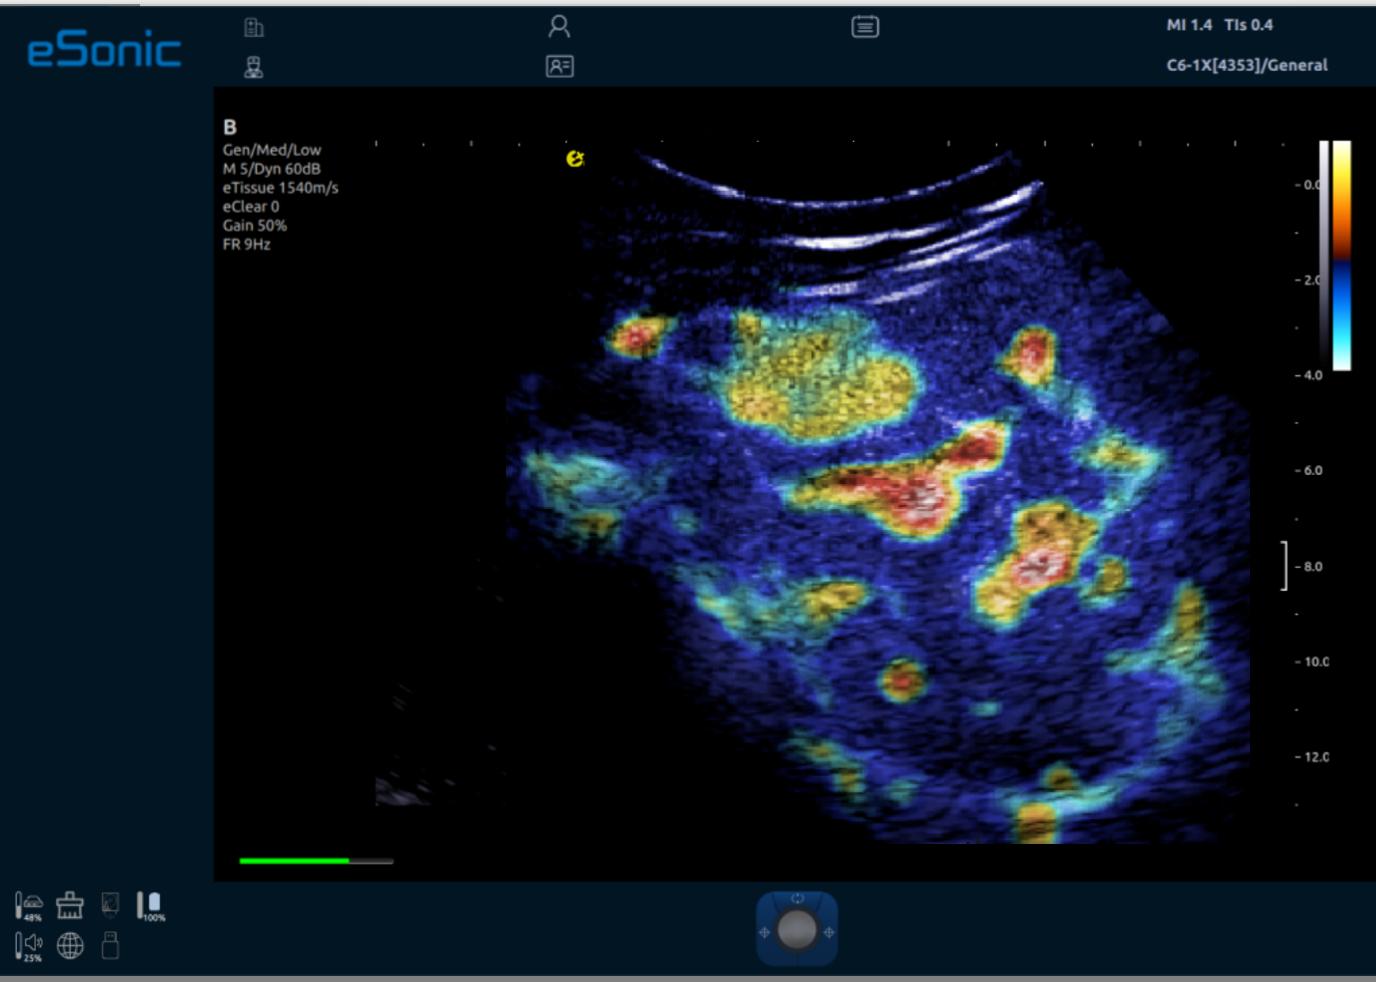

iPlane Contrast 超快速造影成像

AI Contrast 造影智能定量分析软件